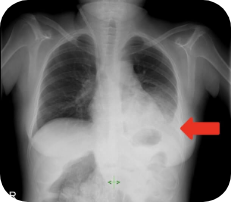

Chest X-ray on admission

showed that Fatima had

fluid accumulating in her

lower left lung

Images supplied with permission of treating clinician.